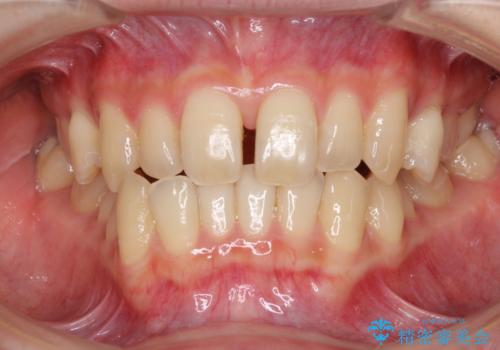

- 奥歯の反対咬合を気にして来院された患者様です。

反対咬合は上顎骨の幅が下顎骨よりも小さいことが原因なので、拡大装置により骨幅を広げて上下関係を改善し、その後インビザラインにて歯並びを整えることとしました。